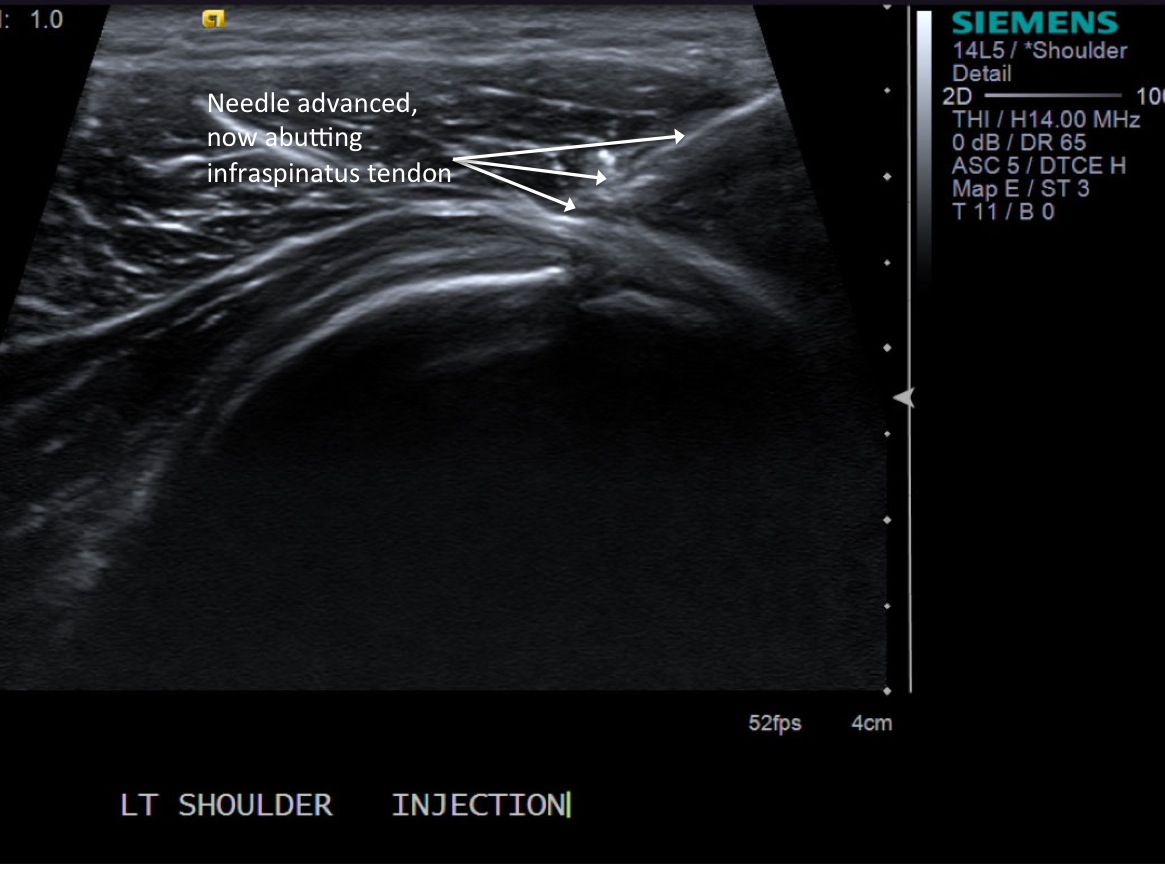

• descriptiondescription

• Needle has been advanced and is about to broach the infraspinatus tendon. If one were to do a test injection at this point, there would be resistance to flow.